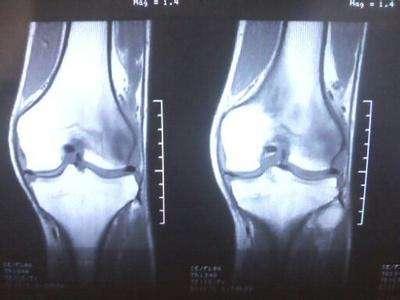

很多人以为步行的运动量较低,虽然每天走上几万步不会对身体造成多大的负担。其实不然,进行过量步行会使身体受到伤害,尤其是对膝盖的磨损。

过度运动导致的 膝关节扭伤和多种关节内损伤可能引起骨膜炎。滑膜的功能异常会导致关节液无法正常生成和吸收,膝关节就会产生积液。滑膜的形态改变还会侵袭膝关节软骨,不及时治疗会导致膝关节骨性关节炎,存在很大的致残危机。